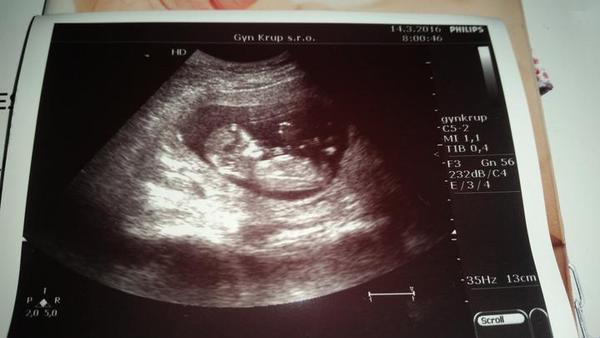

@himanka Ale jo, může být 😊 Nejlépe je to tedy vidět z profilu, můj přiložený ultrazvuk je z 12+3 tt.